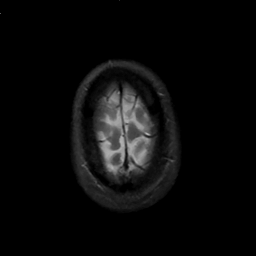

MR Study #1, February 10, 1991 -- Slice #46

[Home][Help][Clinical][Tour 1][Tour 2] Slice 46